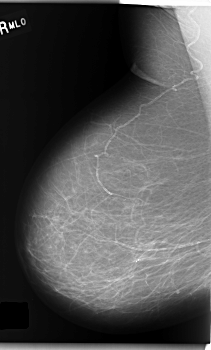

C_0204_1.RIGHT_MLO

RIGHT_CC LINES 5912 PIXELS_PER_LINE 3688 BITS_PER_PIXEL 12 RESOLUTION 50 NON_OVERLAY

RIGHT_MLO LINES 5944 PIXELS_PER_LINE 3584 BITS_PER_PIXEL 12 RESOLUTION 50 NON_OVERLAY